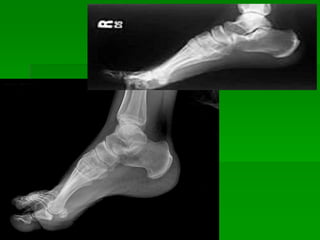

Fractura de 1/3 distal de peroné

Fractura en 1/3 distal de peroné y tibia

Subluxación tibio astragalina